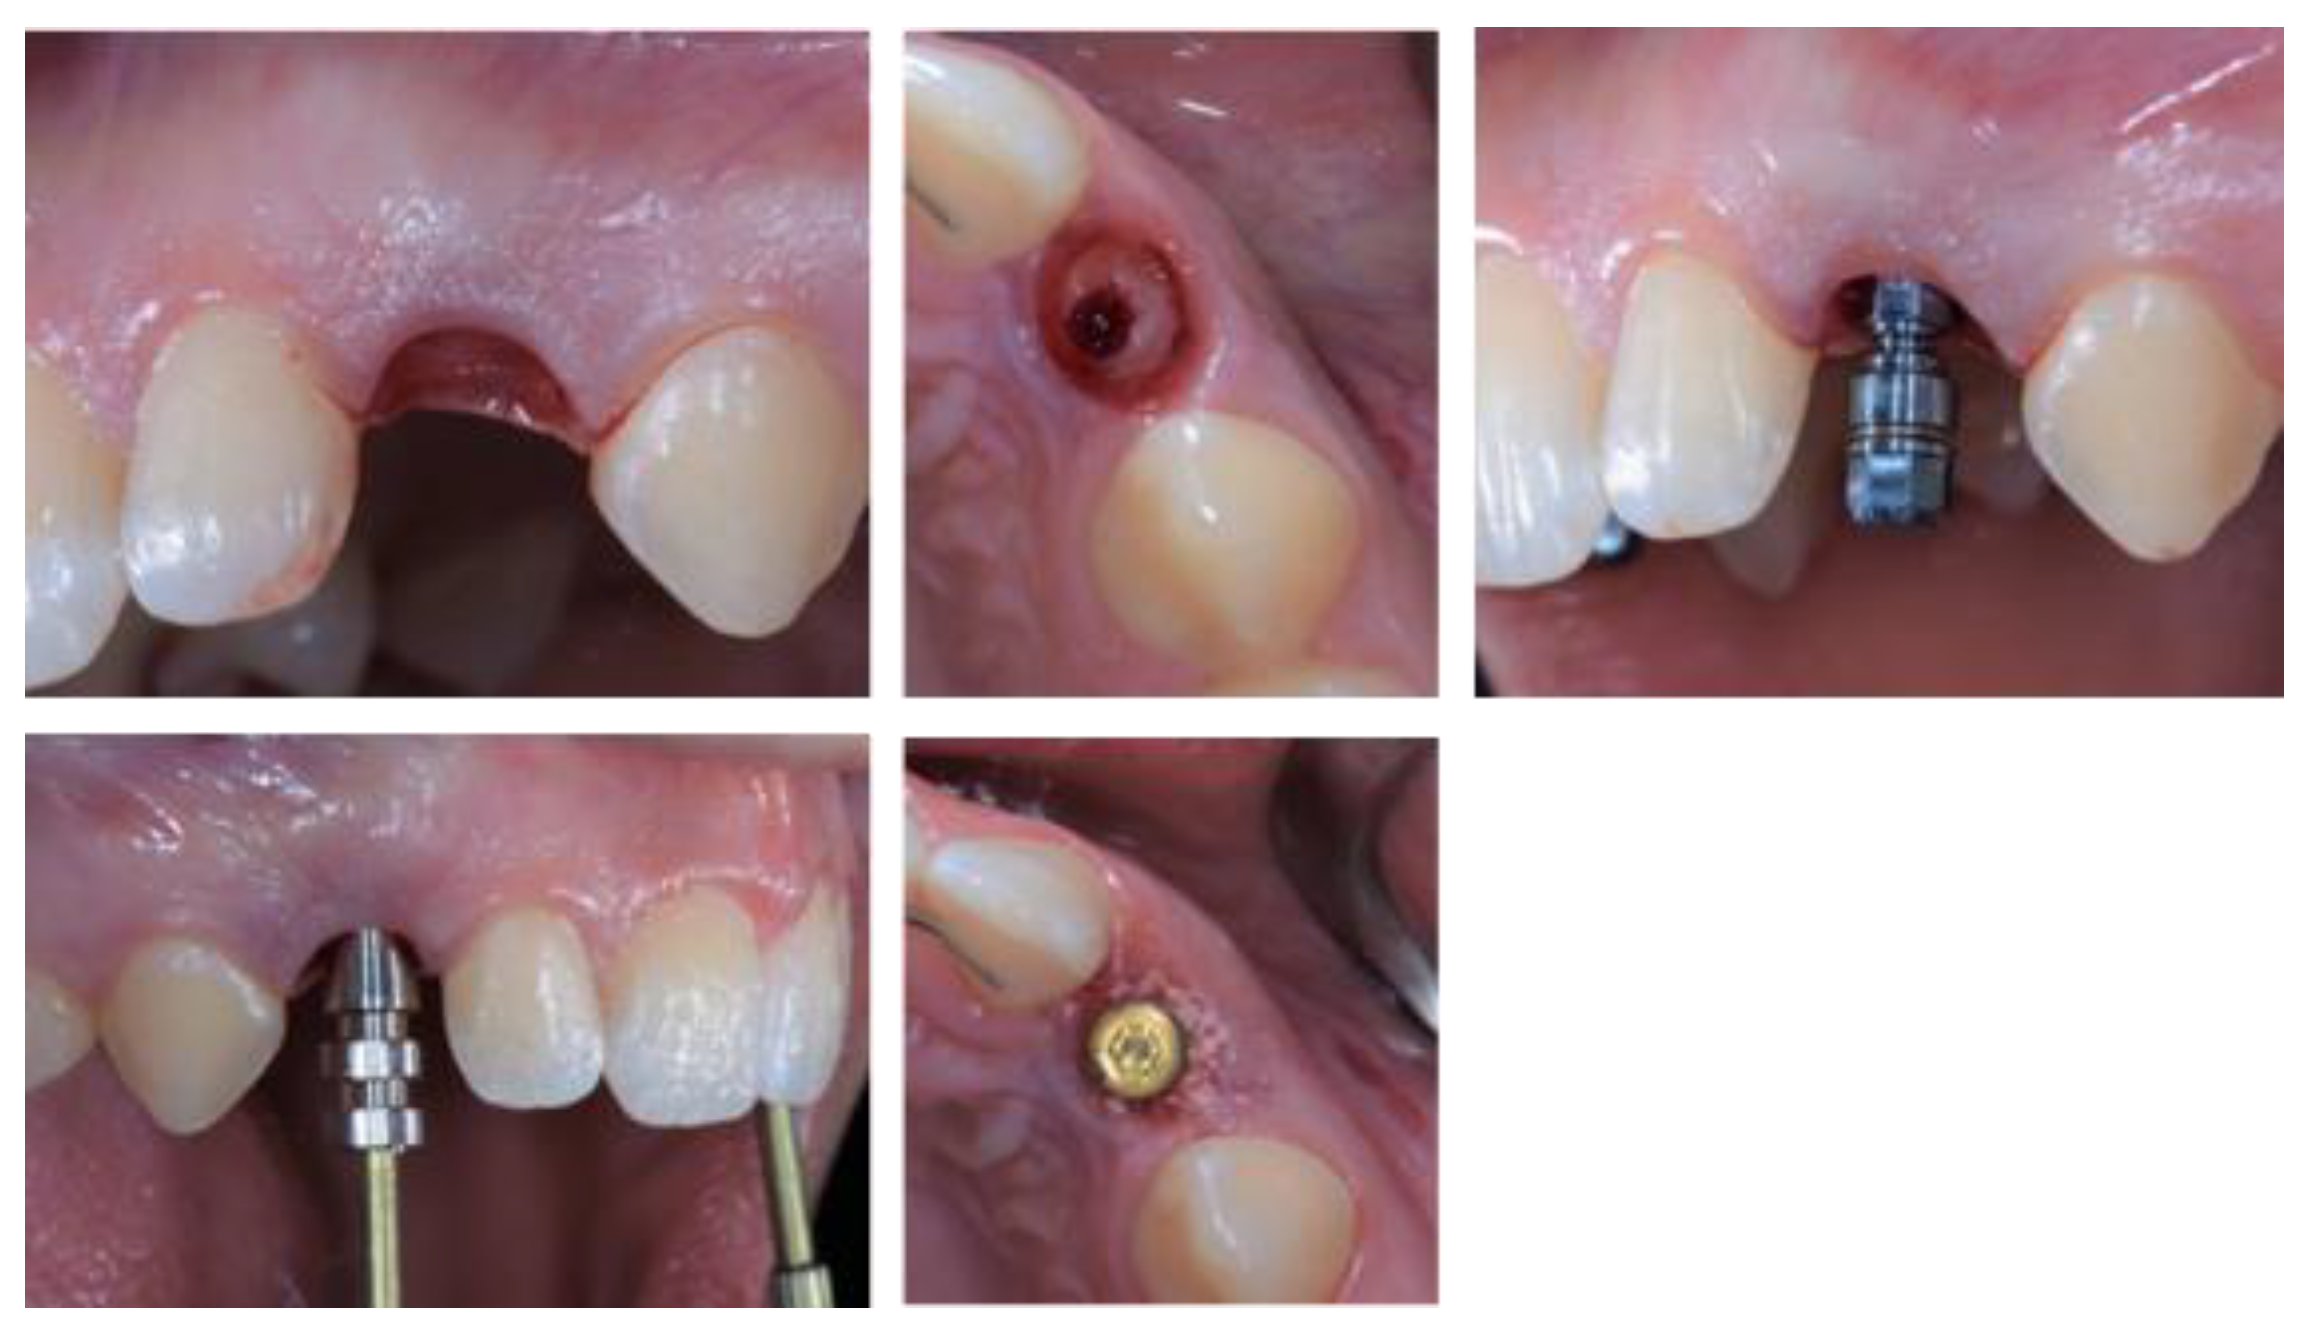

- Case 1:

- Case 2:

- Case 3:

- Case 4:

- Case 5: